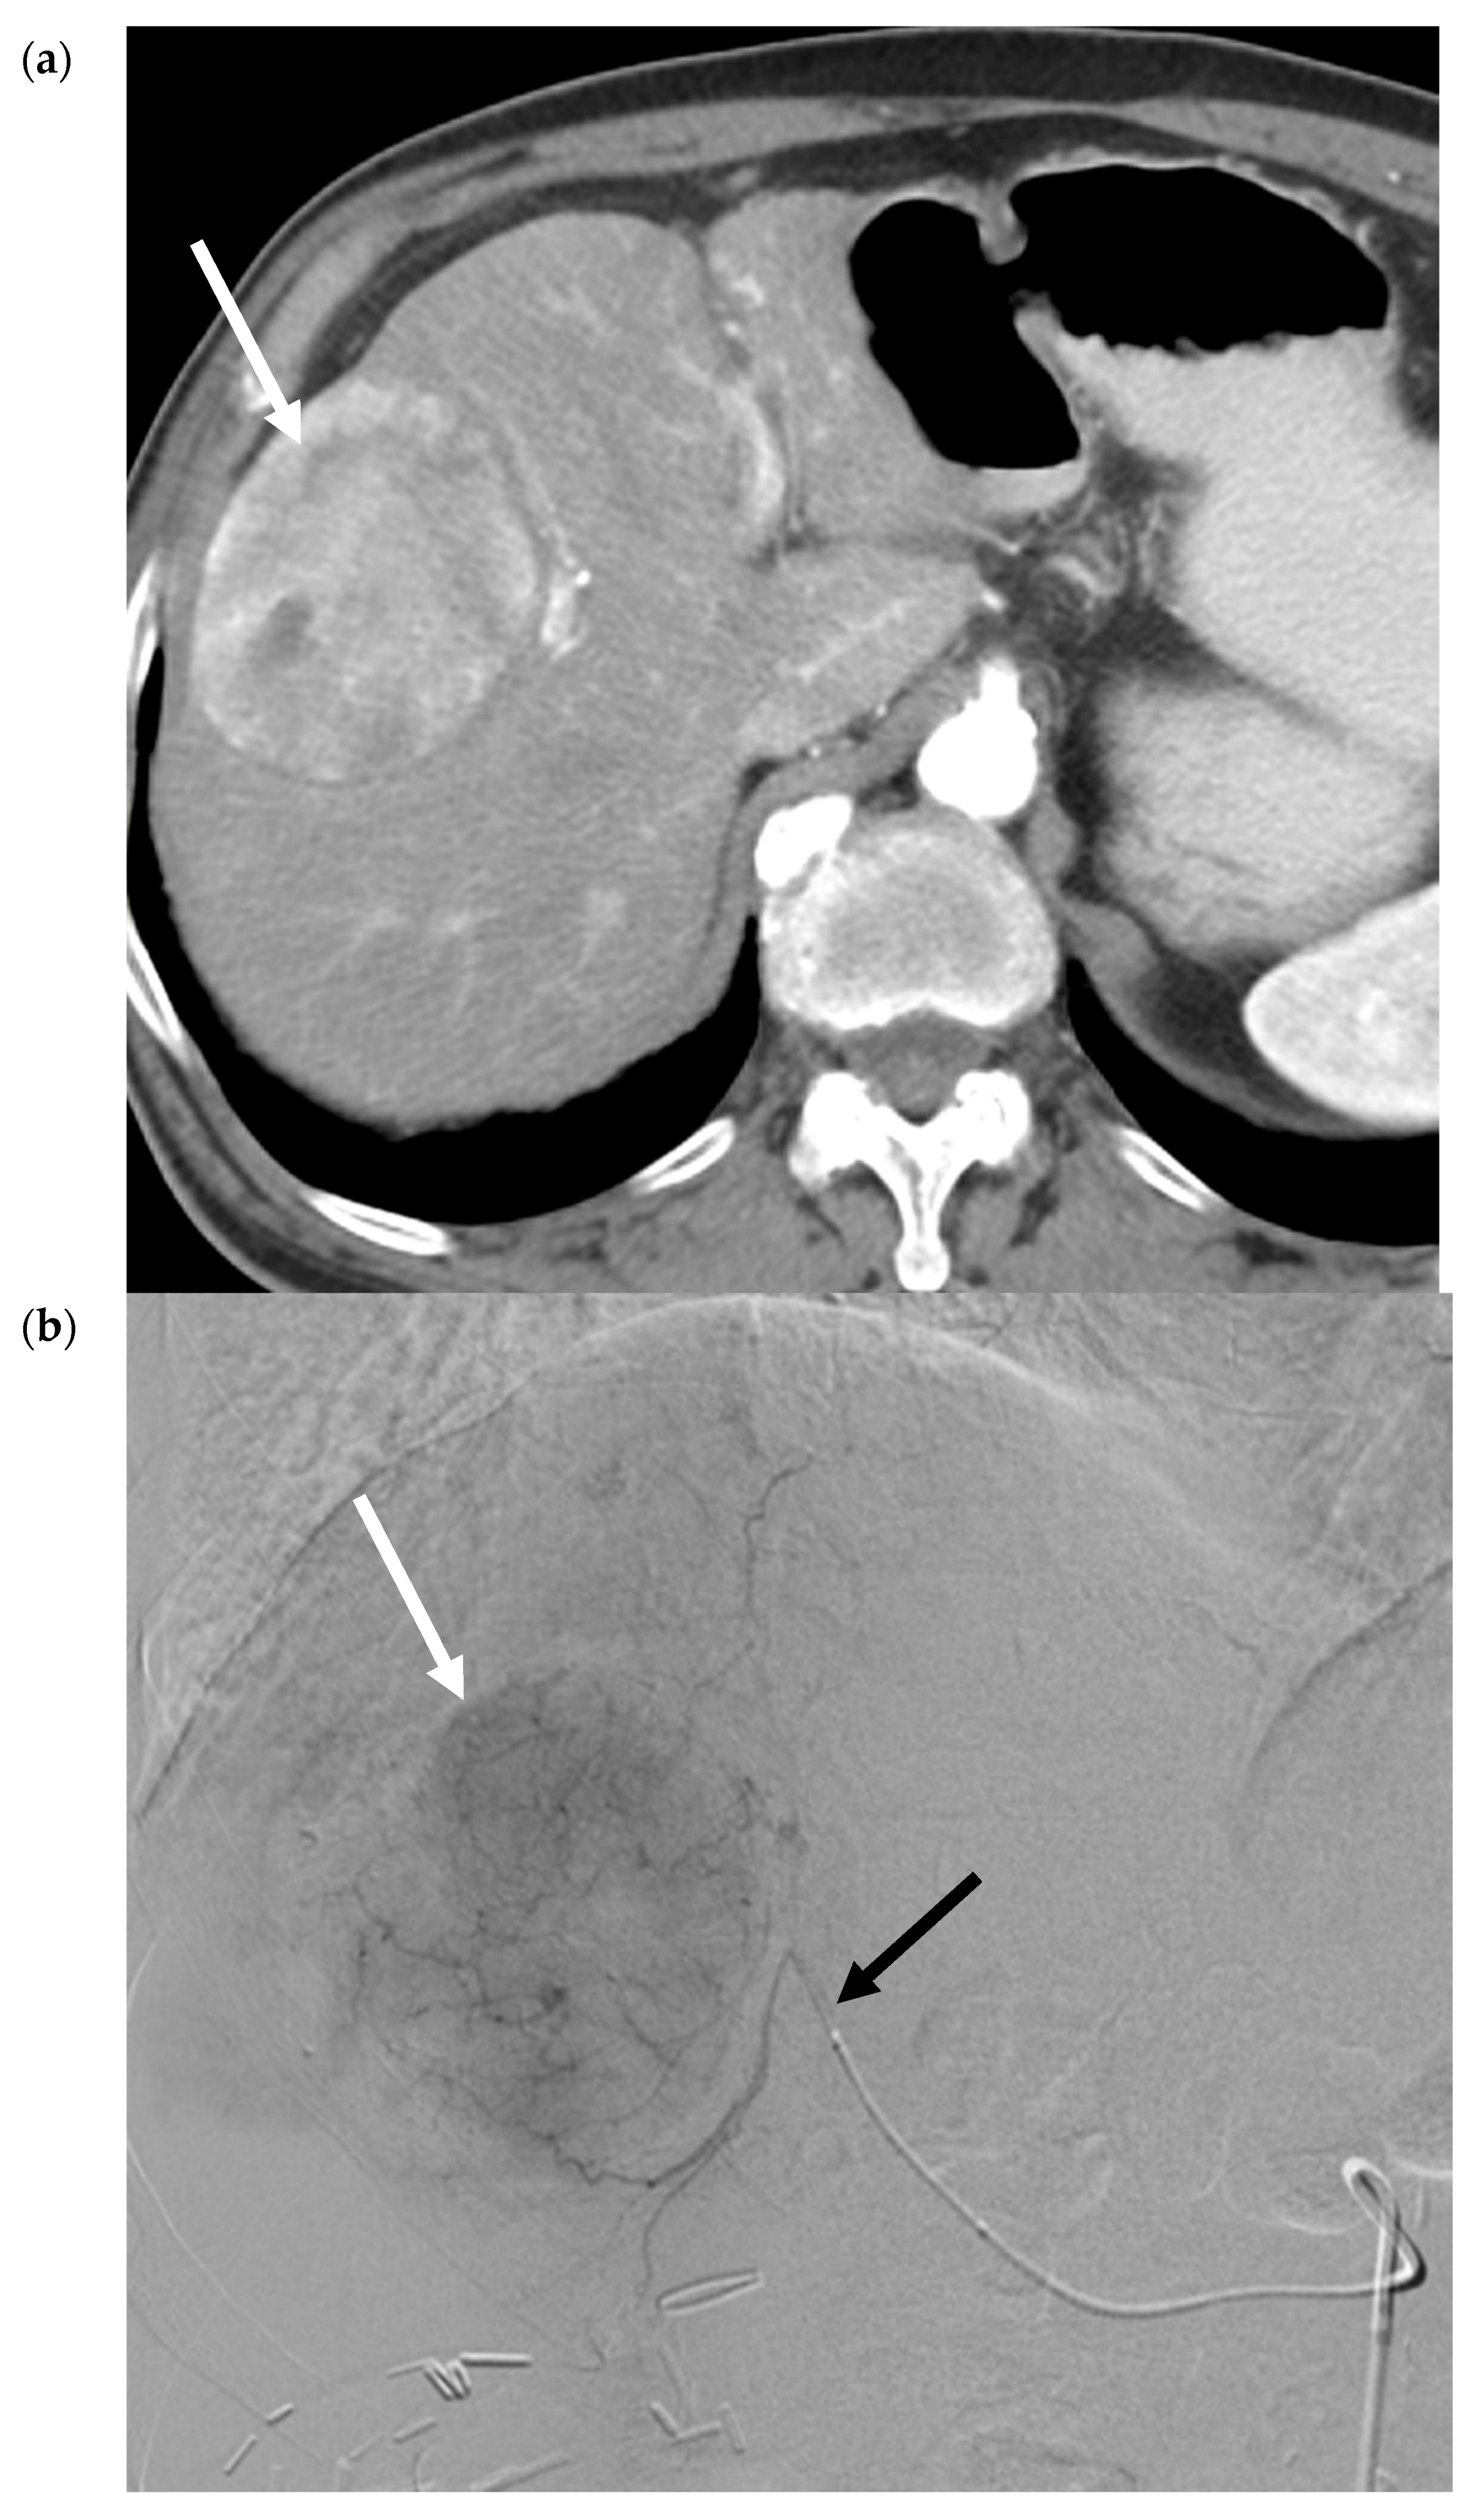

- Vouche, M.; Lewandowski, R.J.; Atassi, R.; Memon, K.; Gates, V.; Ryu, R.K.; Gaba, R.C.; Mulcahy, M.F.; Baker, T.; Sato, K.; et al. Radiation lobectomy: Time-dependent analysis of future liver remnant volume in unresectable liver cancer as a bridge to resection. J. Hepatol. 2013, 59, 1029–1036. [Google Scholar] [CrossRef]

- Riaz, A.; Gates, V.; Atassi, B.; Lewandowski, R.; Mulcahy, M.F.; Ryu, R.K.; Sato, K.T.; Baker, T.; Kulik, L.; Gupta, R.; et al. Radiation Segmentectomy: A Novel Approach to Increase Safety and Efficacy of Radioembolization. Int. J. Radiat. Oncol. 2011, 79, 163–171. [Google Scholar] [CrossRef]

- Lewandowski, R.; Gabr, A.; Abouchaleh, N.; Ali, R.; Al Asadi, A.; Mora, R.; Kulik, L.; Ganger, D.; Desai, K.; Thornburg, B.; et al. Radiation Segmentectomy: Potential Curative Therapy for Early Hepatocellular Carcinoma. Radiology 2018, 287, 1050–1058. [Google Scholar] [CrossRef]

- Vouche, M.; Habib, A.; Ward, T.J.; Kim, E.; Kulik, L.; Ganger, D.; Mulcahy, M.; Baker, T.; Abecassis, M.; Sato, K.T.; et al. Unresectable solitary hepatocellular carcinoma not amenable to radiofrequency ablation: Multicenter radiology-pathology correlation and survival of radiation segmentectomy. Hepatology 2014, 60, 192–201. [Google Scholar] [CrossRef]

- Biederman, D.M.; Titano, J.J.; Korff, R.; Fischman, A.; Patel, R.S.; Nowakowski, F.S.; Lookstein, R.; Kim, E. Radiation Segmentectomy versus Selective Chemoembolization in the Treatment of Early-Stage Hepatocellular Carcinoma. J. Vasc. Interv. Radiol. 2018, 29, 30–37. [Google Scholar] [CrossRef]